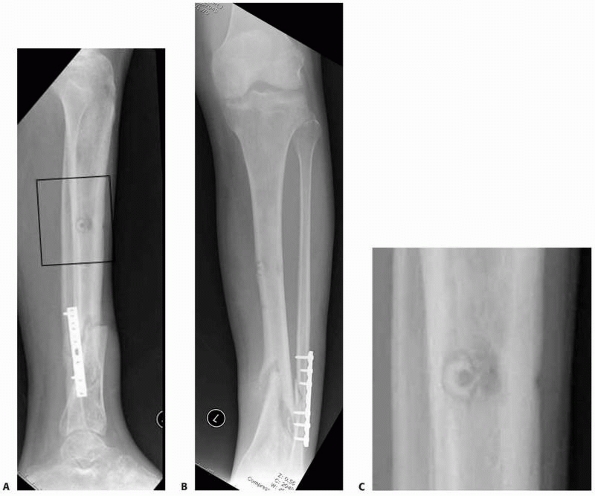

FIGURE 8-16 A,B.

Nonunion with varus deformity following failure of hybrid external fixation. Self-drilling pins used in the diaphysis resulted in a ring sequestrum at proximal pin site (black box). C. Sclerotic bone (dead) at old pin location, with circumferential lucency characteristic of ring sequestrum. This complication required excision of the infected sequestrum. |